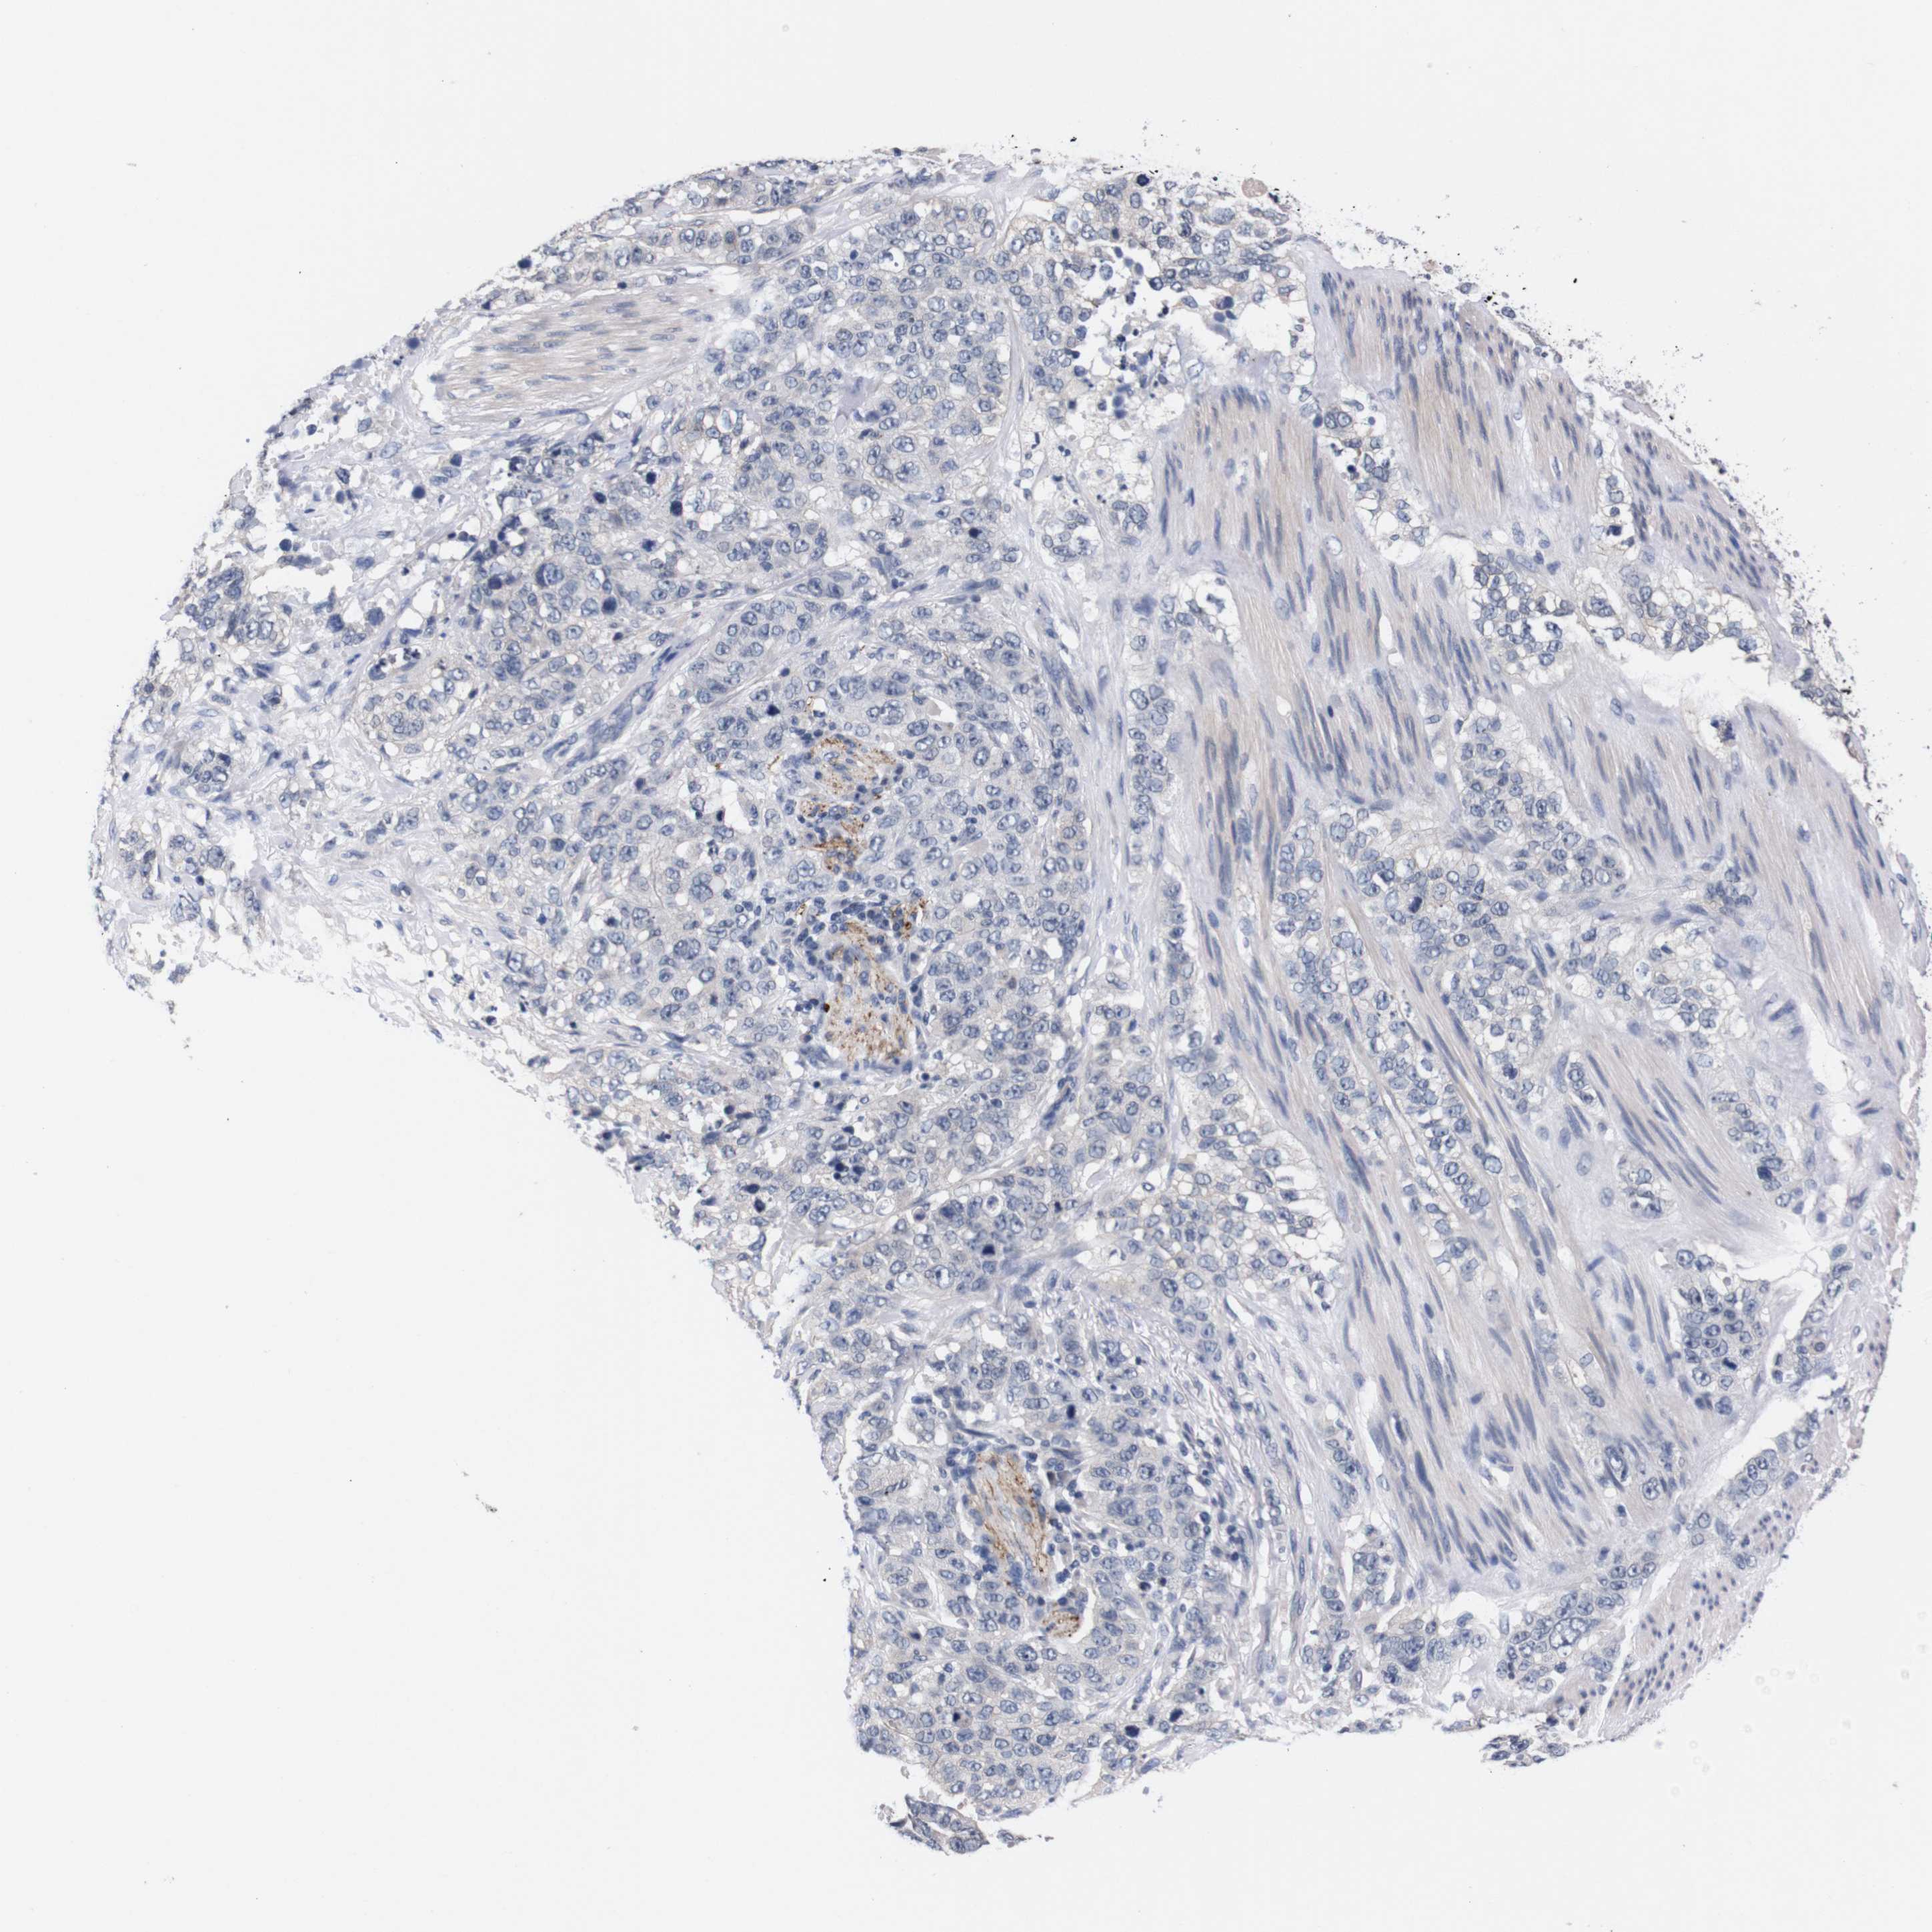

STOMACH CANCER - Protein expressioni

A mouse-over function shows sample information and annotation data. Click on an image to view it in a full screen mode. Samples can be filtered based on level of antibody staining by selecting one or several of the following categories: high, medium, low and not detected. The assay and annotation is described here.

Antibody stainingi

Antibody staining in the annotated cell types in the current human tissue is reported as not detected, low, medium, or high, based on conventional immunohistochemistry profiling in selected tissues. This score is based on the combination of the staining intensity and fraction of stained cells.

Each image is clickable and will lead to virtual microscopy that enables deeper exploration of all samples and also displays staining intensity scores, fraction scores and subcellular localization as well as patient and tissue information for each sample.

Antibody HPA006746

Antibody CAB009805

Staining

High

Medium

Low

Not detected

Intensity

Strong

Moderate

Weak

Negative

Quantity

>75%

75%-25%

<25%

None

Location

Nuclear

Cytoplasmic/membranous

Cytoplasmic/membranous,nuclear

Adenocarcinoma, NOS

Adenocarcinoma, High grade